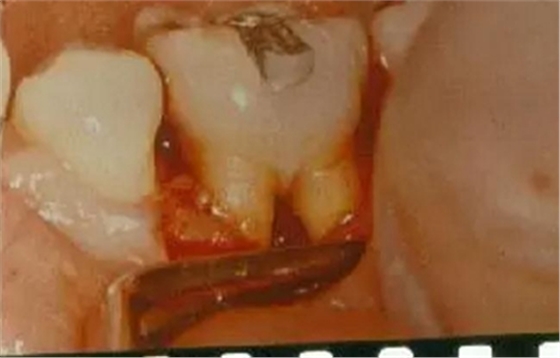

操作方法:

用普通的彎探針或專門設計的Nabers探針探查多根牙的分叉區(qū)。檢查上頜磨牙時,先探查頰側中央處的根分叉區(qū),再從腭側分別探查近中和遠中的根分叉區(qū),但有的會有變異,需從頰側探入;檢查下頜磨牙時,從頰側和舌側中央處分別探查根分叉區(qū)。探查的內容應包括:探針能否水平方向探入分叉區(qū),水平探入的深度,分叉的大小,有無釉質突起,根柱的長度,根分叉區(qū)是否有牙齦覆蓋,注意檢查根分叉區(qū)是否暴露。

牙周袋和骨吸收波及根分叉區(qū),可從臨床上探查到。主要根據(jù)探診和X線片來判斷病變的程度。Glickman將其分為四度,此分類法有利于指導治療和判斷預后。

Ⅰ度:從牙周袋內已能探到根分叉的外形,但尚不能水平探入分叉內,在X線片上看不到分叉區(qū)牙槽骨的吸收醫(yī)`學教育網(wǎng)搜集整理。

Ⅱ度:分叉區(qū)骨吸收僅限于頰側或舌側,或頰舌側均有吸收但尚未與對側相通,根分叉區(qū)內尚有部分牙槽骨和牙周膜存在。臨床探查時探針可從水平方向部分地進入分叉區(qū)內,但與對側不相通,X線片一般僅顯示分叉區(qū)的牙周膜增寬,或骨質密度有小范圍的降低。

Ⅲ度:根分叉區(qū)的牙槽骨全部吸收,形成“貫通性”病變,探針能水平通過分叉區(qū),但它仍被牙周袋軟組織覆蓋而未直接暴露于口腔。下頜磨牙的Ⅲ度病變在X線片上可見完全的透影區(qū),但有時會因牙根靠近或外斜線的重疊而使病變不明顯。

Ⅳ度:根間骨隔完全破壞,且牙齦退縮而使病變的根分叉區(qū)完全暴露于口腔。X線片所見與Ⅲ度病變相似。